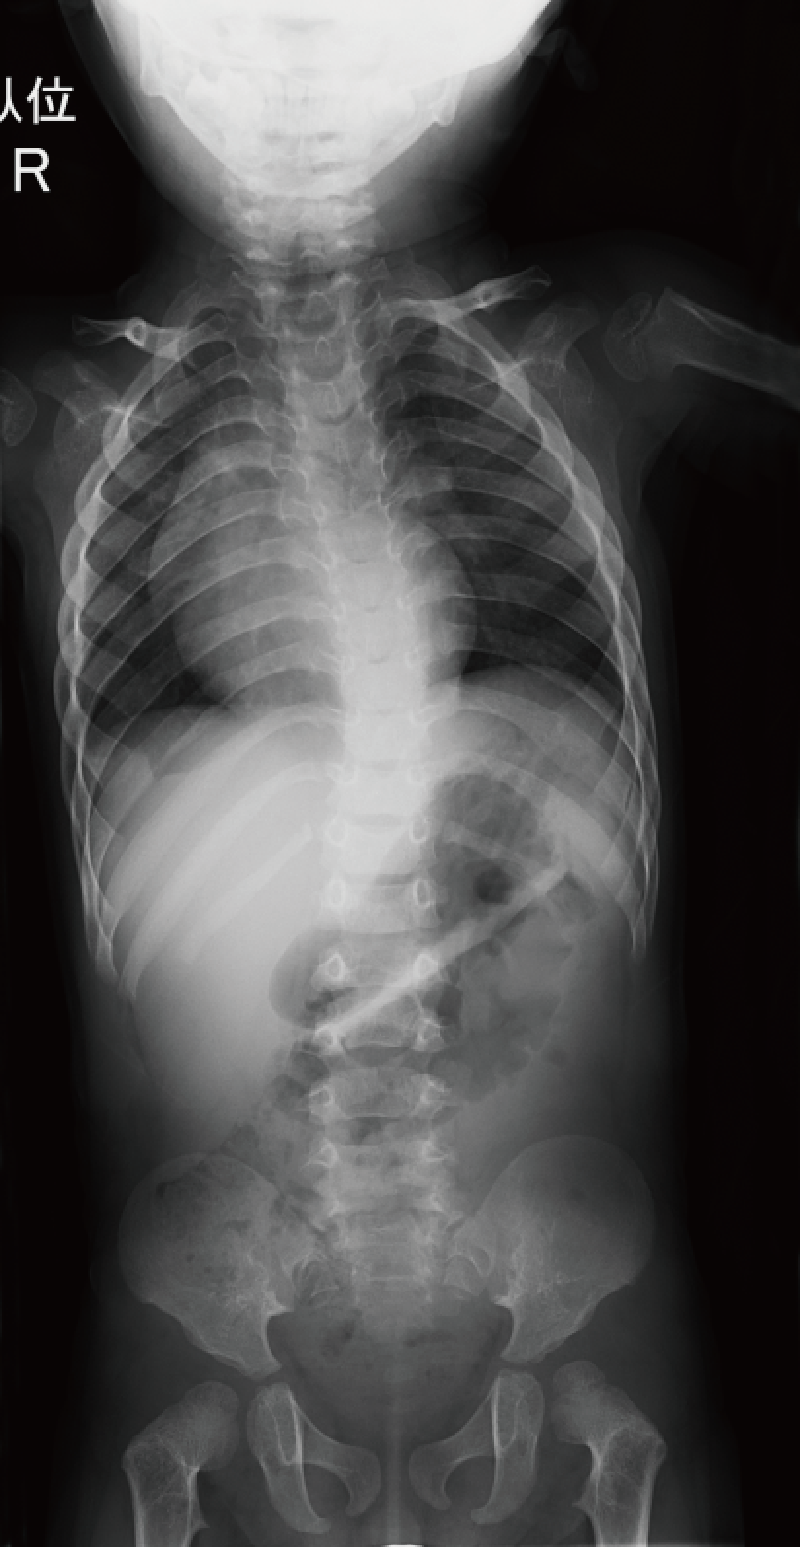

整形外科的臨床所見/特異顔貌および眼・耳などの合併症など:特異顔貌(卵型で平坦な顔、青色強膜、眼球突出など)を呈する。皮膚は柔らかく、筋緊張は低下する。進行性の脊柱変形があり(A)、下肢アライメント異常を呈することがある(B)。

特徴的な画像所見:扁平椎、腸骨低形成、軽度の骨幹端flaringが乳児期にみられる。橈骨頭亜脱臼も多くみられる。

年長児では骨端変形を認めることがある。

A. 全脊柱正面像(11歳、女):著明な脊柱側弯を認める。

B. 両下肢正面像(7歳、女):軽度の外反膝と骨端不整を認める。